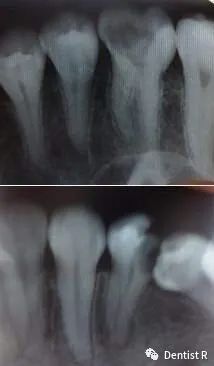

这是很严重的龋齿,已经接近牙神经了!

根管治疗的患牙是拍片的常客了

整个过程至少要拍3张牙片。第一张为了确定是否需要治疗,

同时了解牙根长度和走向

第二张用来测量根管长度,同时确定根管预备是否到位

第三张为了检测治疗效果,观察充填是否到位